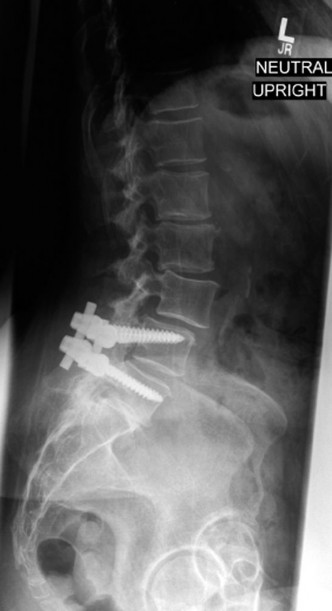

Therefore, the gold standard, definitive treatment for this specific injury pattern is an instrumented posterior fusion. By placing pedicle screws above and below the fractured level, we can utilize ligamentotaxis to partially reduce the retropulsed fragment, restore vertebral height, and rigidly recreate the posterior tension band. This is where the concept of preventing Adjacent Segment Degeneration (ASD) enters our operative planning. If we fuse this patient in 25 degrees of segmental kyphosis, we will create a flatback deformity. The adjacent unfused segments (particularly L2-L3 and L3-L4) will be forced into hyperlordosis to compensate, leading to accelerated facet arthropathy, disc degeneration, and eventual adjacent segment failure. Our surgical goal is not just stabilization, but the meticulous restoration of regional sagittal alignment.

The final, critical step is rod contouring and reduction. To prevent future Adjacent Segment Degeneration, the titanium rods must be contoured to match the patient's ideal pelvic incidence and lumbar lordosis. The rods are seated into the proximal screws. Using reduction towers and careful cantilever forces, the rods are seated into the distal screws. This maneuver actively corrects the 25-degree kyphotic deformity, restoring normal sagittal alignment. The construct is cross-linked if necessary, and a robust posterolateral decortication and bone grafting (using local autograft from the laminectomy and allograft) is performed to ensure a solid arthrodesis.

Radiographic follow-up includes upright AP and lateral plain films before discharge to verify the maintenance of sagittal alignment and hardware integrity. The patient is discharged home or to acute inpatient rehabilitation depending on their functional mobility.

Long-term follow-up at 6 weeks, 3 months, 6 months, and 1 year will focus on assessing fusion mass consolidation and monitoring for any signs of hardware failure. More importantly, long-term surveillance (2 to 5 years post-op) will focus on the adjacent segments. By having meticulously restored the sagittal vertical axis (SVA) and regional lordosis during the index procedure, we have minimized the abnormal shear and compressive forces on the T10-T11 and L3-L4 discs, drastically reducing the patient's risk of developing Adjacent Segment Degeneration requiring revision surgery.